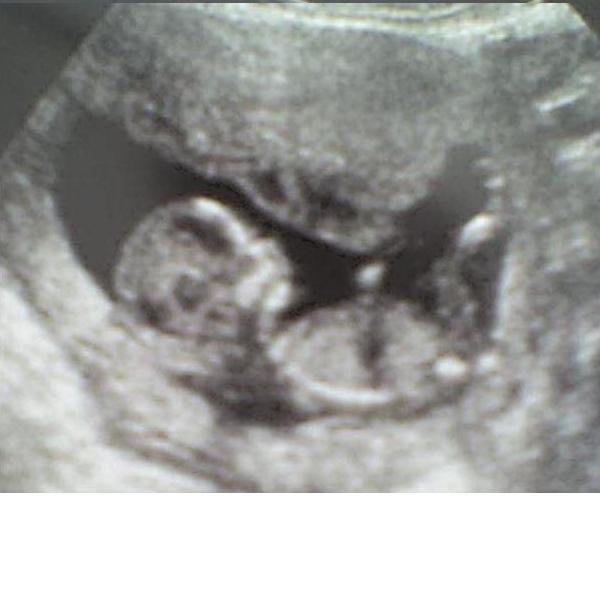

Rögtön hívtam a dokimat,aki azt mondta azonnal menjek be a kórházba!Először megvizsgált és azt mondta ne nagyon reménykedjek,mert túl sok a vér,de azért nézzük meg UH-n is mi a helyzet!Szerencsére a babám még megvolt,12mm,szívműködés látható!Haematoma nem látható!Kórházi felvétel lett,fenyegető vetéléssel!